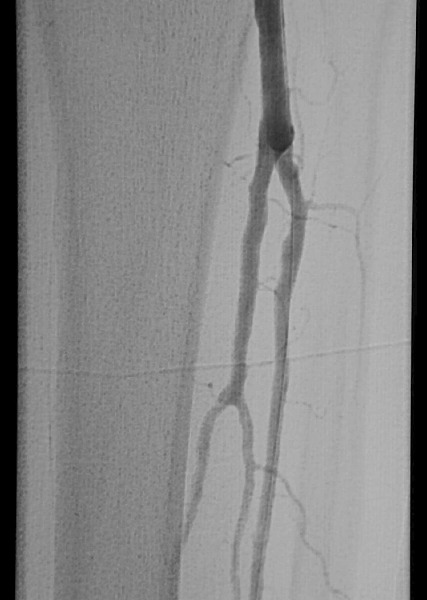

After completing angiogram procedures, surgeons performed an antegrade puncture of the left common femoral artery and placed a 6-Fr sidearm sheath with its tip in the proximal superficial femoral artery. A repeat diagnostic study confirmed the previous findings. The team subsequently used a 4-Fr Berenstein catheter with glide coating (Boston Scientific) loaded with a .014-inch guidewire (Sparta/Core 14, Guidant Corp.) to catheterize the anterior tibial artery and cross the stenosis. The vascular surgeons performed cryoplasty therapy with a 3 mm by 20 mm PolarCath Peripheral System balloon (CryoVascular Systems, Inc.). A post-op control angiogram showed excellent results with a less than 10 percent residual stenosis and no angiographic evidence of dissection. The vascular surgeons proceeded to turn their attention toward the occluded segment of the anterior tibial artery. They advanced the 4-Fr glide Berenstein catheter across the aforementioned treated segment and placed the tip of the catheter just above the occluded portion of the artery. After injecting contrast, the surgeons documented reconstitution of the post-obstructed anterior tibial artery. The surgical team crossed the obstructed segment with a 0.035-inch straight, stiff Glidewire (Boston Scientific), advanced the catheter across the obstruction and confirmed its intraluminal position with a contrast injection. Using the 3.0 mm balloon, they treated the obstructed segment with cryoplasty therapy. A post-op control angiogram disclosed minimal residual stenosis and no vessel wall dissection. There was no evidence of distal embolization of plaque fragments. The vascular surgeons advanced the 0.014 inch guidewire through the balloon catheter and crossed the stenosis of the dorsalis pedis artery again, utilizing a roadmap technique. They treated the stenosis of the dorsalis pedis artery at and below the ankle with a 2.5 mm by 20 mm CryoPlasty balloon. A post-op control angiogram showed significant improvement in the diameter of the dorsalis pedis artery with a focal area of spasm at its mid-portion. The patient tolerated the procedure well and the multidisciplinary team noted a strong, palpable dorsalis pedis pulse after the procedure.